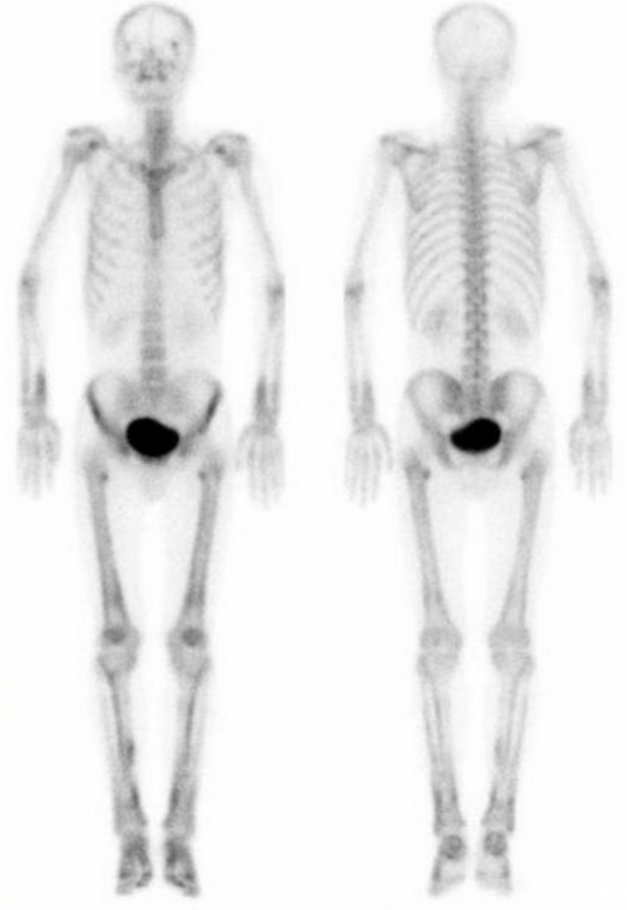

正常骨显像

全身多发骨转移

超级骨显像

肺性肥大性骨关节病